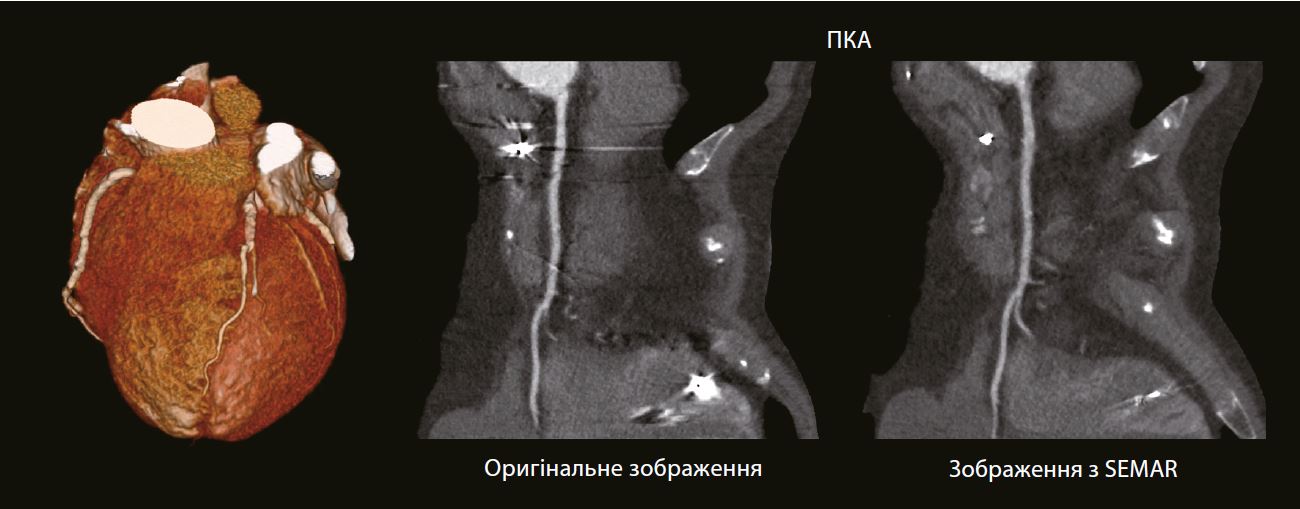

69-річний чоловік з кардіостимулятором і протезом аортального клапана звернувся з болем у грудях. Для виключення ішемічної хвороби серця було призначено КТ-ангіографію коронарних судин.

Проксимальна права коронарна артерія частково закрита артефактами. Артефакти, спричинені металевими електродами кардіостимулятора, які більше не видно на реконструкції з використанням SEMAR. Стеноз судини не візуалізується.

EКГ-aдаптований SEMARTM (Технологія зниження артефактів від металу) долає одну з невирішених проблем у КТ візуалізації коронарних артерій у пацієнтів з імплантованими серцевими пристроями, такими як кардіостимулятори та дефібрилятори.

Використовуючи протокол сканування зі звичайним дозовим навантаженням на пацієнта та унікальний процес реконструкції, SEMAR може зменшити металеві артефакти, які інакше могли б заважати візуалізації найближчих коронарних артерій.